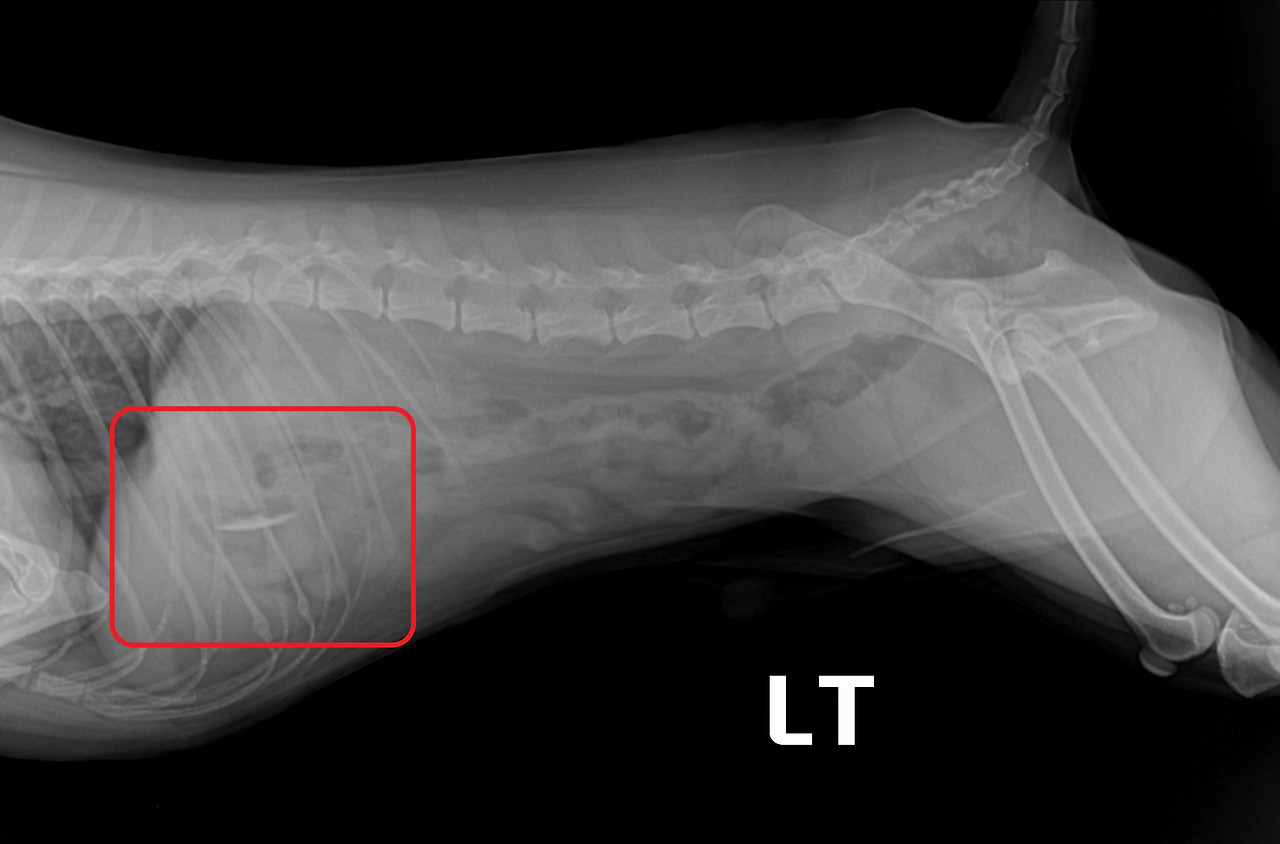

KakaoTalk_20200529_124300684.jpg

KakaoTalk_20200529_124252695.jpg

<좌> 위에 플라스틱이 들어있는 경우, <우> 위에 이어폰이 들어 있는 경우

사진출처 : 24시 센트럴 동물 메디컬센터

"치료는 어떤 식으로 이루어지나요?"

먹어도 되는 음식이 식도에 걸린 경우에는 위 내로 밀어 넣어서 소화를 시키게 됩니다.

먹어선 안 될 이물이라면 내시경이나 수술을 하게 됩니다.

위 내 이물의 경우는 대부분 내시경을 통해 꺼낼 수 있지만 크기가 커서 내시경으로 꺼내기 힘든 경우도 있어요.

이럴 때는 이물을 위 내로 밀어 넣고 나서 위 절개 수술을 통해 제거하게 됩니다.

만약 이물이 소장에 걸렸다면 위험하기 때문에 반드시 수술을 통해 이물을 제거해야 해요.